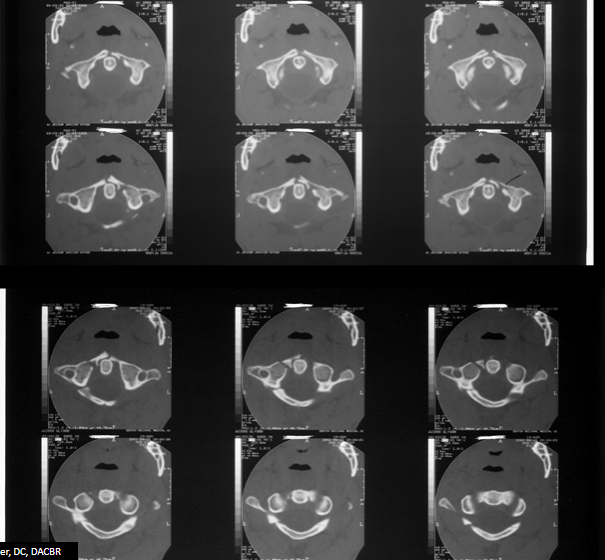

17

Q

What are two radiographic findings in this view?

What is the diagnosis?

A

• Offset of lateral atlantoaxial alignment

• Wide paraodontoid space

Jefferson fracture

C1 burst fracture